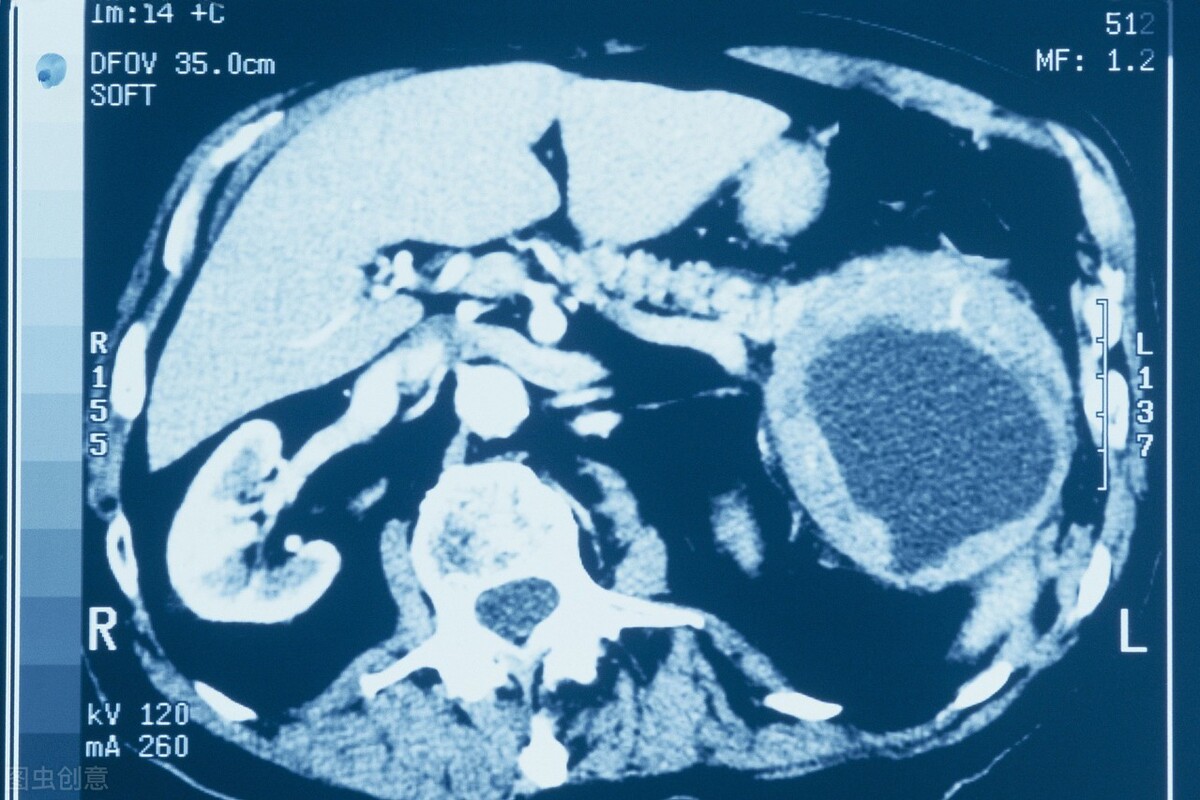

患者平均年龄为53岁,其中男性77例(40.1%),女性115例(59.9%)。所选患者的CA199中位数为136.5单位/毫升。为确定CA199升高的原因,进行了以下检查:胸部X线191例,胸部CT32例,腹部CT192例,磁共振6例,PET-CT4例,腹部超声78例,妇科超声45例,胃镜76例,结肠镜24例。

在唯一一例肝囊肿中,囊肿大小10厘米,压迫导致胆道扩张,该患者的CA199水平升高至460.2 U/毫升,并在随访期间持续升高,但是没有恶性肿瘤迹象。